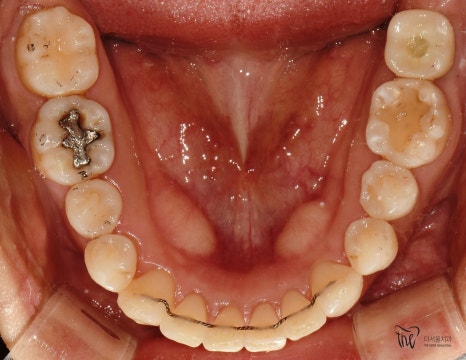

교합면에서 봤을 땐, 교정치료를 떠나서

선행해야 될 치료들이 많다는 것을 알 수 있습니다.

아말감이 수복 되어있던 곳의, 아말감 탈락에

따른 치질이 드러나 있다던지, 교합면의

다발성 우식증에 따라서 충치치료도 같이

병행을 해야 되는 상황입니다.

다만 하나 아쉬운 점은,

사랑니의 맹출 위치 불량에 따라서

바로 앞에 있는 제2 대구치는 발치 결정을

내리게 되었습니다.

이미, 치축이 상당히 쓰러져 있는 상황이며

업라이팅을 해드리기에는 시간이 오래 걸릴뿐더러

예후 또한 좋지 않을것으로 판단이 되어서

부정교합 2급 치료가 다 끝나는 시점에 맞춰서,

임플란트로 대체를 해드리기로 했죠.